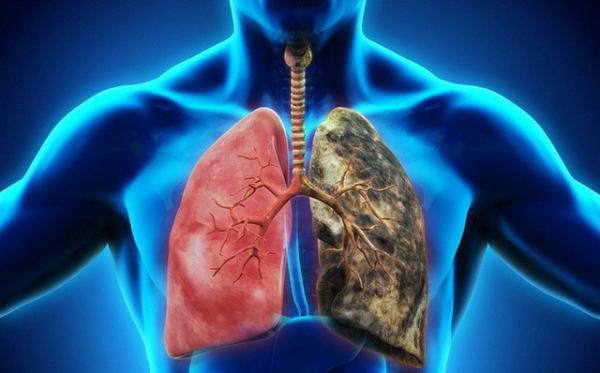

Cô gái trẻ qua đời sau 5 ngày phát hiện ung thư. Chuyên gia đă lên tiếng cảnh báo liên quan tới vấn đề này. Cô gái trẻ đi khám phát hiện ung thư phổi giai đoạn cuối và đă quá muộn.

Khi được chẩn đoán bị ung thư phổi t́nh trạng của bệnh nhân đă vô cùng nặng, không c̣n thời gian để phẫu thuật và hóa trị. Chỉ trong 5 ngày, hơi thở của cô gái trẻ dần yếu đi và qua đời.

Ung thư phổi biểu mô tuyến

Là h́nh thức ung thư phổi phổ biến với phụ nữ, đặc biệt được phát hiện ở những người không hút thuốc, dưới 45 tuổi và hầu hết là người châu Á. Kiểu khác của loại ung thư phổi này là ung thư phổi phế nang được t́m thấy ở những phụ nữ trẻ không hút thuốc. Hiện nay ung thư phổi biểu mô tuyến vẫn ngày một tăng khi ung thư phổi biểu mô tế bào có dấu hiệu giảm.

Nguyên nhân các bệnh ung thư phổi nói chung một phần đều do hút thuốc. Cũng có rất nhiều trường hợp không hút thuốc là do tiếp xúc radon bên trong nhà. Ung thư phổi biểu mô tuyến là sự kết hợp nhiều yếu tố khác nhau.

Cách nhận biết ung thư phổi biểu mô tuyến

Thông thường, ung thư phổi biểu mô tuyến thường bắt đầu từ các mô nằm bên ngoài phổi. Khi mới h́nh thành, chúng ít bị phát hiện do không gây ra các triệu chứng đặc biệt. Những dấu hiệu mắc bệnh sớm như mệt mỏi, khó thở, đau lưng, vai…rất dễ bị bỏ qua.

Chỉ đến khi bệnh đă trở nên trầm trọng th́ các dấu hiệu đặc trưng của ung thư phổi như ho lâu ngày, ho ra m.á.u mới bắt đầu xuất hiện. V́ vậy, để phát hiện bệnh sớm, hăy chú ư những triệu chứng sau: